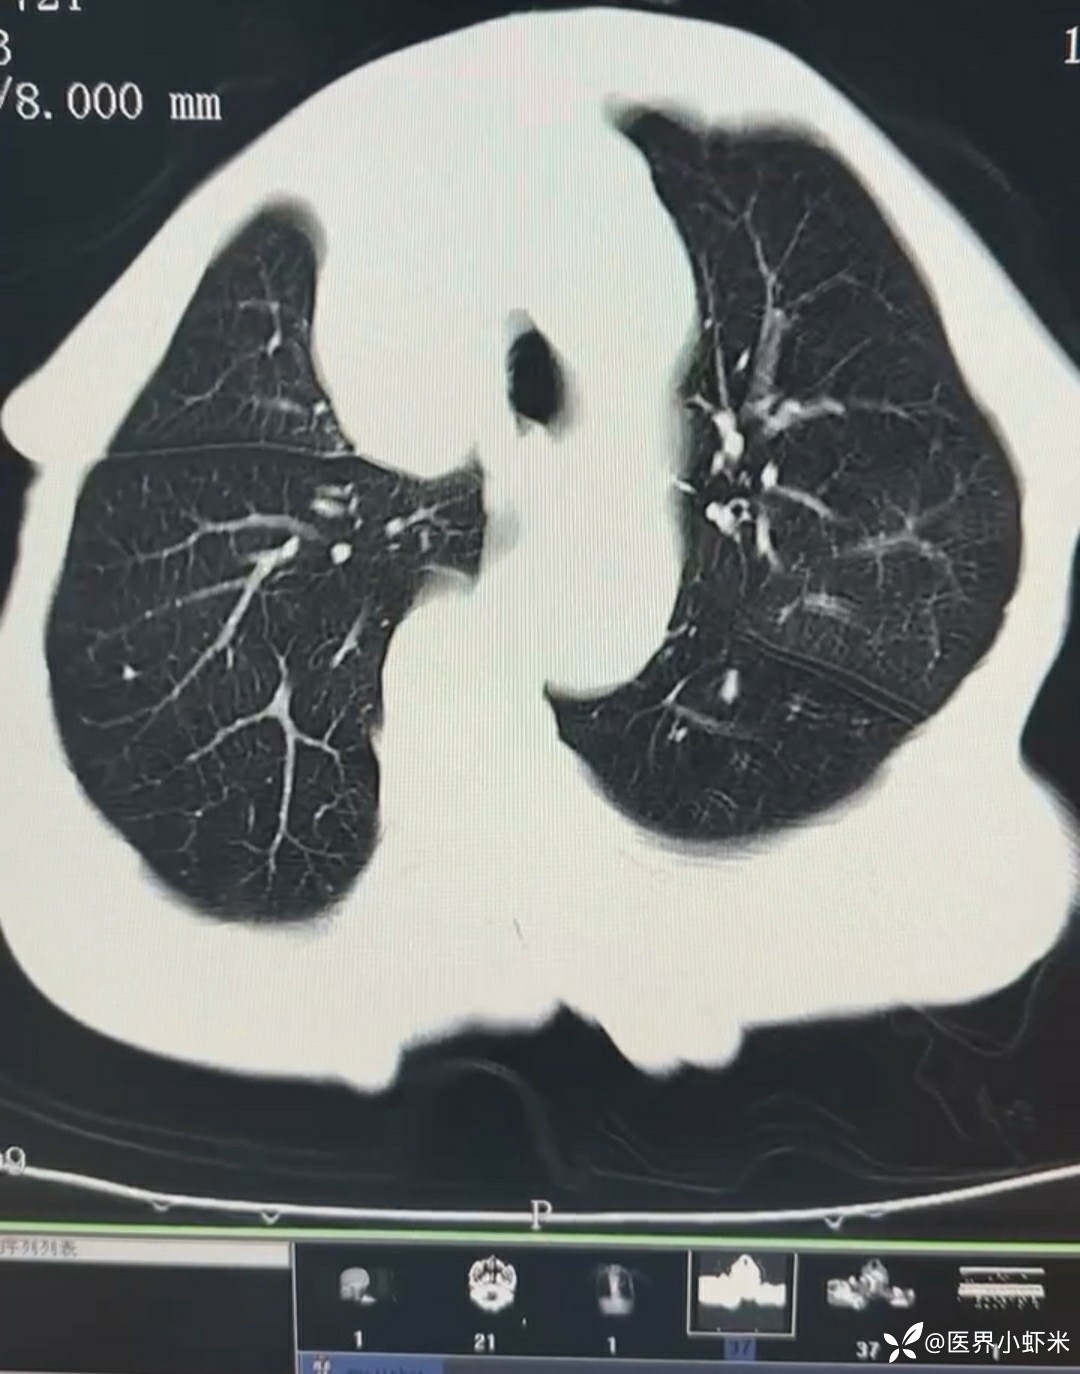

长期大量吸烟,日吸烟3包左右,喜食碳酸饮料,不喝酒。

目前考虑:1.中央型肺癌伴2.肝继发恶性肿瘤?2.左丘脑继发恶性肿瘤?3.左丘脑出血?4.肾功能不全5.肝功能异常6右肾萎缩7.肺部感染8.慢性阻塞性肺病7.高血压3级(极高危)。